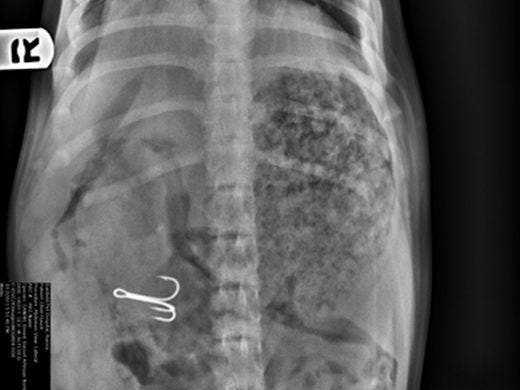

There is nothing worse than seeing your pet suffer from vomiting or diarrhea. These cases can range from mild cases of gastritis from eating garbage to severe cases of pancreatitis that can sometimes be fatal. Every case is different so we tailor the testing to the patient to come up with the best treatment plan. In some cases, normal x-rays and blood-work can spot the problem, in other cases we need to use an experienced ultrasonagrapher and barium radiology. Many of these cases need to spend the night in the hospital and will be checked frequently by the staff as well as have 24 hour video monitoring.